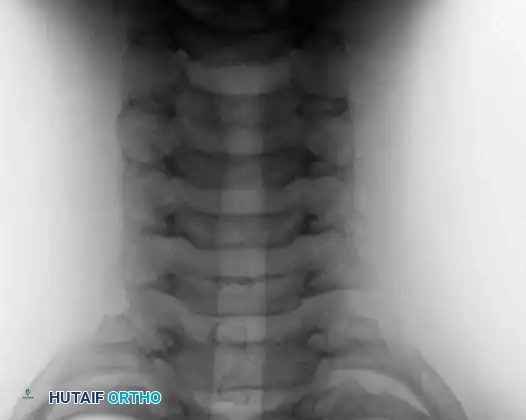

Postoperative anteroposterior and lateral radiographs following marginal resection of the C3 osteoblastoma, demonstrating complete tumor removal and restoration of cervical alignment.